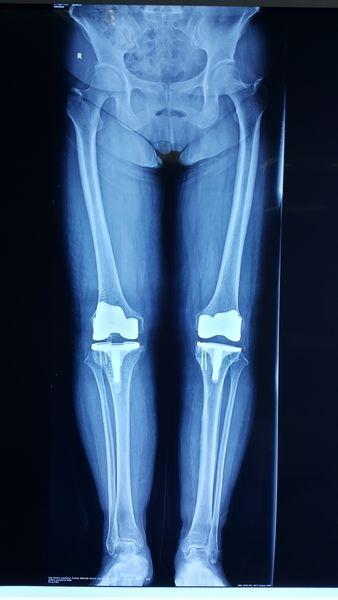

前些日子 , 帮妈朋友所在的医院里就迎来了一位特殊的患者 。 这位特殊的患者是一位10岁的小女孩 , 孩子的妈妈带着她来医院进行检查 。 经过医生一系列的检查 , 结果却让人大吃一惊 。 医生告诉孩子的妈妈 , 女孩的骨缝已经闭合了 , 换句话说就是这个女孩虽然才10岁 , 身体却已经停止长高了 。